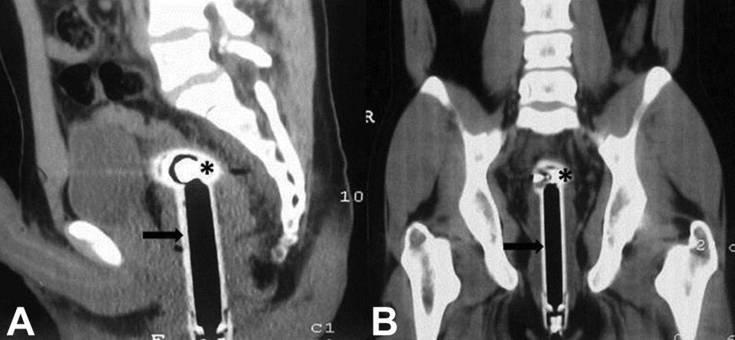

Ο άντρας κατέληξε σε πανεπιστημιακό και ερευνητικό νοσοκομείο του Νέου Δελχί, όπου διαπιστώθηκε η καλή του κατάσταση, καθώς δεν είχε υποστεί εσωτερική αιμορραγία. Η περίπτωσή του δημοσιεύτηκε στο περιοδικό «British Medical Journal», όπου υπάρχει και η σχετική ακτινογραφία με το τηλέφωνο του μπάνιου μέσα στον οργανισμό του.

Μετά τη μικροεπέμβαση για την αφαίρεση του ξένου σώματος, ο άντρας παρέμεινε στο νοσοκομείο δύο μέρες για προληπτικούς λόγους και στάλθηκε τελικά στο σπίτι του. Ο επικεφαλής γιατρός πάντως δρ Peeyush Kumar, λέγοντας πόσο συχνά επαναλάμβανε ο άντρας ότι το τηλέφωνο είχε σφηνωθεί στον πρωκτό του από την πτώση, έγραψε: